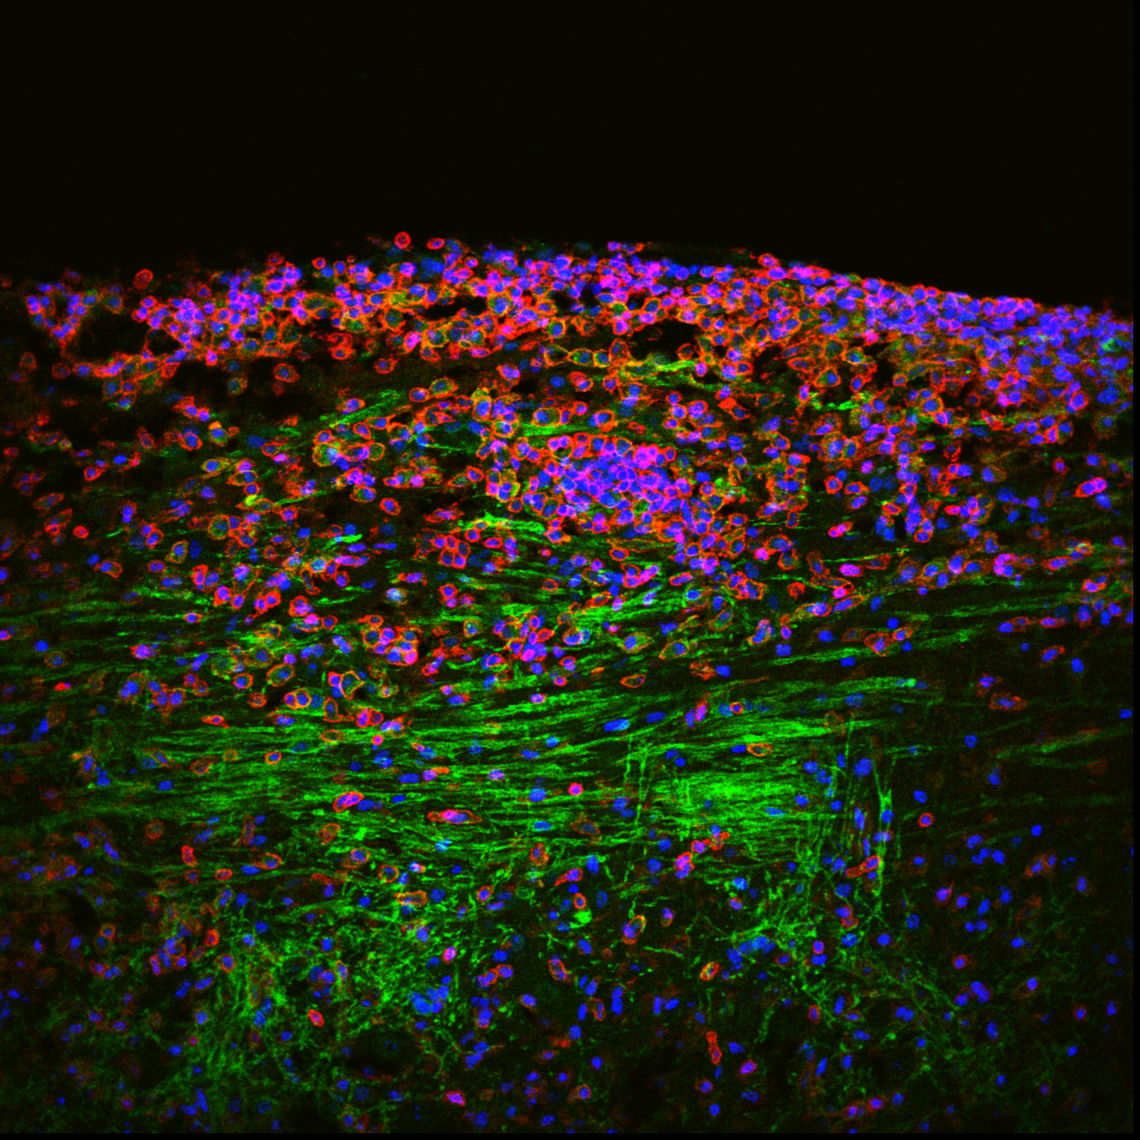

Lipid droplets within phagocytes in LPC spinal cord lesion (day7). CD45 (leukocytes-red), Tdtomato labeled (microglia-gray), lipid droplets (green).

Manoj Mishra

A key determinant of progression of most neurodegenerative diseases including MS is age. Studies have reported the deficient clearance of myelin debris, and increased formation and deposition of cholesterol crystals within macrophages, in the aging CNS after demyelination. This has been associated with reduced expression of cholesterol exporter ABCA1 with age. As myelin contains about 80% of lipids, we propose that the accumulation, deficient processing and shuttling of lipids or lipid droplets contribute to the impaired myelin debris clearance in an injured aging CNS. We aim to address the deficient phagocytosis by macrophage and microglia using CX3CR1 promoter-driven Ai9 mice. In culture we aim to test the handling of myelin-associated lipids on murine and human macrophage/microglia, and then target therapeutically the processing of intracellular lipid. Debris impedes the repair process in the lesion, so this work will help us to achieve bioenergetically conducive environment for the repair.